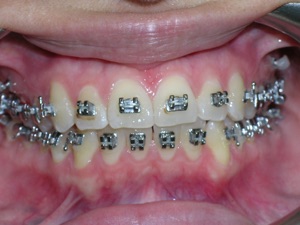

Here’s a case of crowding treated by trimming or narrowing of teeth. Also we utilized temporary anchor devices (mini screws) to help us keep the front teeth from sticking out too much.

Take a look at the braces applied as well as the trimming we did. Elastics were used from the mini screws.